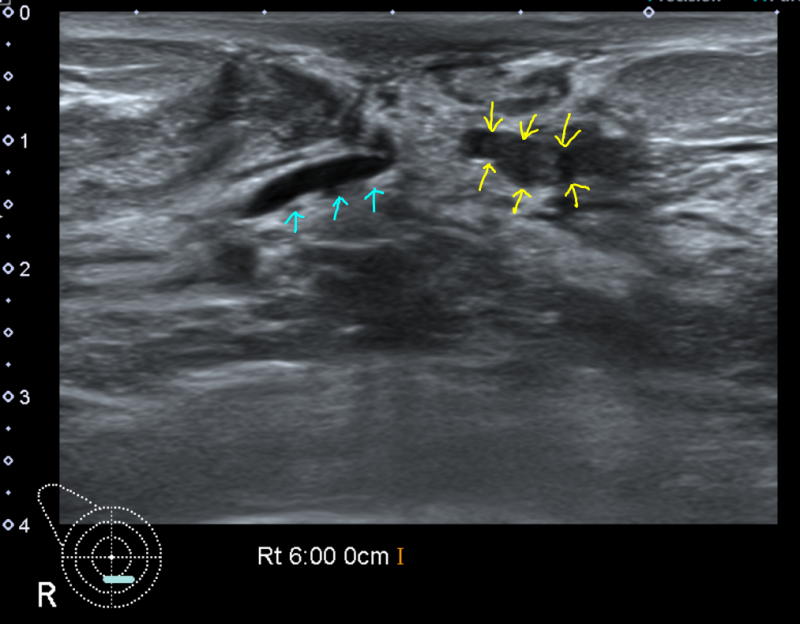

먼저 관내유두종은 유두와 연결된 유관 내부에 용종이 생기는 양성질환이다. 혹이 유두처럼 생겼다고 해서 유두종이라고 부르는데, 크기가 0.5cm 미만, 때로는 1cm 이상으로 매우 작게 발생합니다. 유방의 유두병변은 유두상 모양을 특징으로 하는 병변으로 고립성 유두종, 다발성 말초유두종, 유두종증 등이 있다. 유방암과 양성 유두병변 사이에는 직접적인 관계는 없으나 동시에 발생하거나 차후에 발생하는 유방암이다. 와 관련이 있습니다. 관내 유두종의 비교 유두종에는 일반적으로 단일성 관내 유두종과 다발성 말초 유두종이 포함됩니다. 고립성 관내 유두종은 유두 병변 중에서 가장 흔하며 35~55세의 폐경기 여성에서 가장 자주 발생합니다. 다발성 말초 유두종은 고립성입니다. 유관내 유두종보다 어린 나이에 발생하며, 유두 분비물이 거의 없고, 말초 유관에서 발생합니다. 그 중 15%는 양측성으로 발생합니다. 무엇보다 유방암은 다발성 말초유두종에서 발생할 확률이 높으며, 완전 국소절제술로 치료한다. 따라서 수술을 하면 재발률은 약 24%이다. 관내유두종의 원인 및 증상 관내유두종의 원인은 명확히 알려져 있지 않으나, 주로 30~50대에서 발생합니다. 증식 속도가 빠르고, 여러 개의 종양이 발생하는 경우 악성종양일 가능성이 높으므로 검사하여 제거해야 합니다. 관내 유두종 증상으로는 유두에서 분비물이 나오는데, 이 분비물은 끈적거리고 노란색이며 주스나 혈액과 섞여 있을 수 있습니다. 또는 유륜에 덩어리가 느껴지거나 압력으로 인해 통증이 발생할 수 있습니다. 그러나 증상이 없는 경우도 있다. 있습니다. 관내 유두종의 치료 단순 유두종은 유방 조영술이나 절제 생검으로 쉽게 치료할 수 있습니다. 가장 기본적인 검사로는 유방촬영술과 유방초음파가 있습니다. 유방조영술은 방사선을 통해 사진을 찍는 검사이며, 유방초음파는 유방 관련 증상을 치료하는 데 사용됩니다. 초음파를 통해 결절의 크기와 모양을 확인하는 검사법입니다. 발견된 결절이 악성인지 양성인지 확인하기 위해 생검을 실시합니다. 분비물이나 통증으로 인해 관내유두종이 의심된다면 부담 없이 내원하셔서 치료를 받아보시길 권해드립니다. 광주가슴수술 안내 오늘은 광주가슴수술 목뉴방수술과 ‘관내유두종 증상 및 치료’에 대해 알아봤습니다. 여러분께 도움이 되길 바라며, 광주가슴성형목뉴방외과에서는 차별화된 의료장비와 전문적인 지식을 환자분들에게 제공하겠습니다. 섬세한 진료를 약속드립니다. (진료시간) 월~화~수~금 : 09:00~19:00 목요일 : 09:00~20:00 토요일 : 09:00~14:00*목요일 야간진료는 9:00~20시 :00. 이를 실시하고 있습니다. 더 자세한 내용을 알고 싶거나 치료에 대해 궁금한 점이 있으시면 아래 홈페이지나 목뉴방외과의원을 방문해주세요. 감사합니다. 목뉴외과의원 목뉴외과의원은 유방암, 갑상선암 진단검사부터 암수술까지 원스톱으로 진행하는 광주전남 유일의 유방, 내분비외과입니다. 차별화된 첨단 의료장비와 풍부한 의료 경험을 바탕으로 세밀한 진료 시스템을 제공합니다. 고객님의 소중한 목과 가슴의 문제를 해결하고 건강증진을 위해 노력하고 있습니다. www.neckbreast.com 50m NAVER 더보기 /OpenStreetMap 지도데이터 x NAVER /OpenStreetMap Map Controller Legend 부동산 구시군 동시면 산오리읍 도청 목새성형외과 76 광주광역시 서구 죽봉대로 76 메디필센터 광고 후 계속됩니다. 다음 주제 작성자 취소 광주가슴수술 재생 0 좋아요 0 좋아요 공유 0:00:00 재생 음소거 00:00 00:00 실시간 설정 전체 화면 해상도 currentTrack 자막 비활성화 재생 속도 NaNx 해상도 자막 설정 비활성화 옵션 글꼴 크기 배경색 재생 속도 0.5x 1.0x(기본값) 1.5x 2.0x 알 수 없는 오류가 발생했습니다. 도움말이 음소거되었습니다. 도움말 라이센스 이 영상은 고화질로 재생할 수 있습니다. 설정에서 해상도를 변경해보세요. 자세히보기 0:00:00 접힘/펼침 관내유두종 증상 및 치료 광주가슴성형 #광주가슴성형